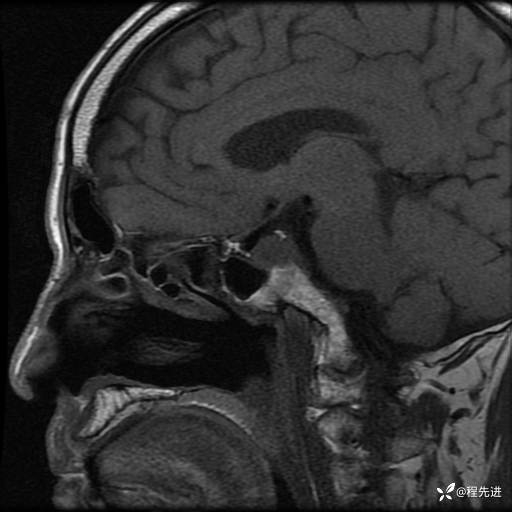

MRI平扫+增强:

T2: